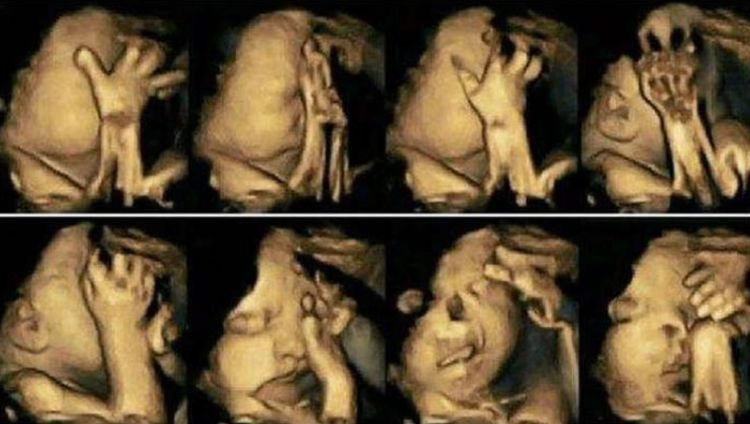

90后,小齐已经怀孕六个多月了。今天,她来医院做了大面积的畸形筛查。通常她常常觉得腹部的婴儿特别活泼动人,整天都在肚子里移动。这次例行检查,小琪并不介意,觉得确定没问题。当她进入B加班时,通过电脑屏幕,医生报告说孩子一直在移动,看不到另一半的脸,而小琪却被孩子们在屏幕上的各个位置逗乐了。心理美女认为这个孩子必须聪明,表现如此小,看起来如此可爱。

医生让小齐出去散步,让孩子露脸,然后来看看。小琪跑出去抽烟,进了B超市。医生闻到烟雾,问她是否吸烟。小琪并不在乎说她的朋友在她身边抽烟,不管是否怀孕。此时,屏幕上的孩子被暴露,很明显有唇裂和腭裂。小琪是差异,但医生建议她堕胎。

医生说:如果孩子动了太多,这并不意味着一定是好事。它也可能在胃中不舒服。他经常摇摆着提醒他的母亲,小琪认为这种情况是无形的。他也开始了解孩子的活力,吸烟并未被打破。你认为你是什么样的母亲?现在孩子有身体缺陷,建议家长清楚地思考,如果它出生,肯定会接受大手术,并且不能恢复正常外观。